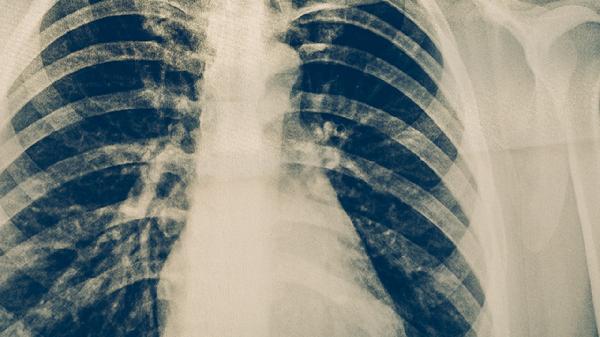

胸部X线检查能发现肺结核引起的肺部病变,如浸润、空洞、纤维化等典型表现。该方法可辅助诊断并评估病变范围和严重程度,但需结合其他检查综合判断,因部分其他肺部疾病也可能出现类似影像学表现。